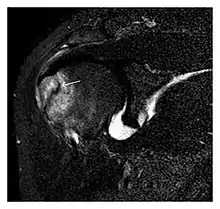

The greater tuberosity of the humerus is also an illustrative location of occult fractures. The osseous injury may follow seizures, glenohumeral dislocation, forced abduction, or direct impaction. They are commonly discovered on MRI in symptomatic patients with suspicion of rotator cuff tear. Coronal images are best suited for detection. They appear as crescentic oblique lines surrounded by a bone marrow edema pattern (Figure 5). The rotator cuff must be inspected since associated ligamentous lesions are common. In the ankle, malleoli and tarsal bones should be checked carefully for any cortical disruptions and radiolucent lines that may reveal a fracture. Awareness of the exact location of the pain will help direct the attention of the interpreter when searching for very subtle signs of fracture (Figure 6).[1]

a

a b

b

Figure 6: Subtle anterior talar fracture in a 39-year-old man presenting with ankle pain after a fall. (a) Anteroposterior radiograph shows a subtle oblique radiolucent line through the talus (white arrows). (b) Sagittal CT reformation confirms the presence of an anterior talar fracture with cortical offset (black arrow). Avulsion fractures, which consist of a detached bone fragment resulting from a ligament or tendon pulling away from the bone, may also present with subtle radiographic signs. Tiny osseous fragments near the presumed attachment site of a ligament suggest this diagnosis. Common sites are the lateral tibial plateau (the Segond fracture), the spinal tuberosity of the tibia resulting from anterior cruciate ligament avulsion, and the ischial tuberosity.[1]